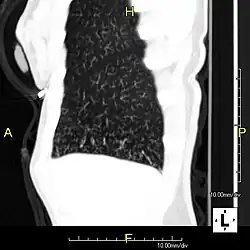

Around 80% of people with primary ciliary dyskinesia experience respiratory problems beginning within a day of birth. Many have a collapsed lobe of the lung and blood oxygen low enough to require treatment with supplemental oxygen.[1] Within the first few months of life, most develop a chronic mucus-producing cough and runny nose.[1] The main consequence of impaired ciliary function is reduced or absent mucus clearance from the lungs, and susceptibility to chronic recurrent respiratory infections, including sinusitis, bronchitis, pneumonia, and otitis media. Progressive damage to the respiratory system is common, including progressive bronchiectasis beginning in early childhood, and sinus disease (sometimes becoming severe in adults). However, diagnosis is often missed early in life despite the characteristic signs and symptoms.[2] In males, immotility of sperm can lead to infertility, although conception remains possible through the use of in vitro fertilization, there also are reported cases where sperm were able to move.[8] Trials have also shown that there is a marked reduction in fertility in females with Kartagener's syndrome due to dysfunction of the oviductal cilia.[9]

Many affected individuals experience hearing loss and show symptoms of otitis media which demonstrates variable responsiveness to the insertion of myringotomy tubes or grommets. Some patients have a poor sense of smell, which is believed to accompany high mucus production in the sinuses (although others report normal – or even acute – sensitivity to smell and taste). Clinical progression of the disease is variable, with lung transplantation required in severe cases. Susceptibility to infections can be drastically reduced by an early diagnosis. Treatment with various chest physiotherapy techniques has been observed to reduce the incidence of lung infection and to slow the progression of bronchiectasis dramatically. Aggressive treatment of sinus disease beginning at an early age is believed to slow long-term sinus damage (although this has not yet been adequately documented). Aggressive measures to enhance clearance of mucus, prevent respiratory infections, and treat bacterial superinfections have been observed to slow lung-disease progression. The predicted incidence is 1 in approximately 7500.[10]

When accompanied by the combination of situs inversus (reversal of the internal organs), chronic sinusitis, and bronchiectasis, it is known as Kartagener syndrome[3] (only 50% of primary ciliary dyskinesia cases include situs inversus).[11]